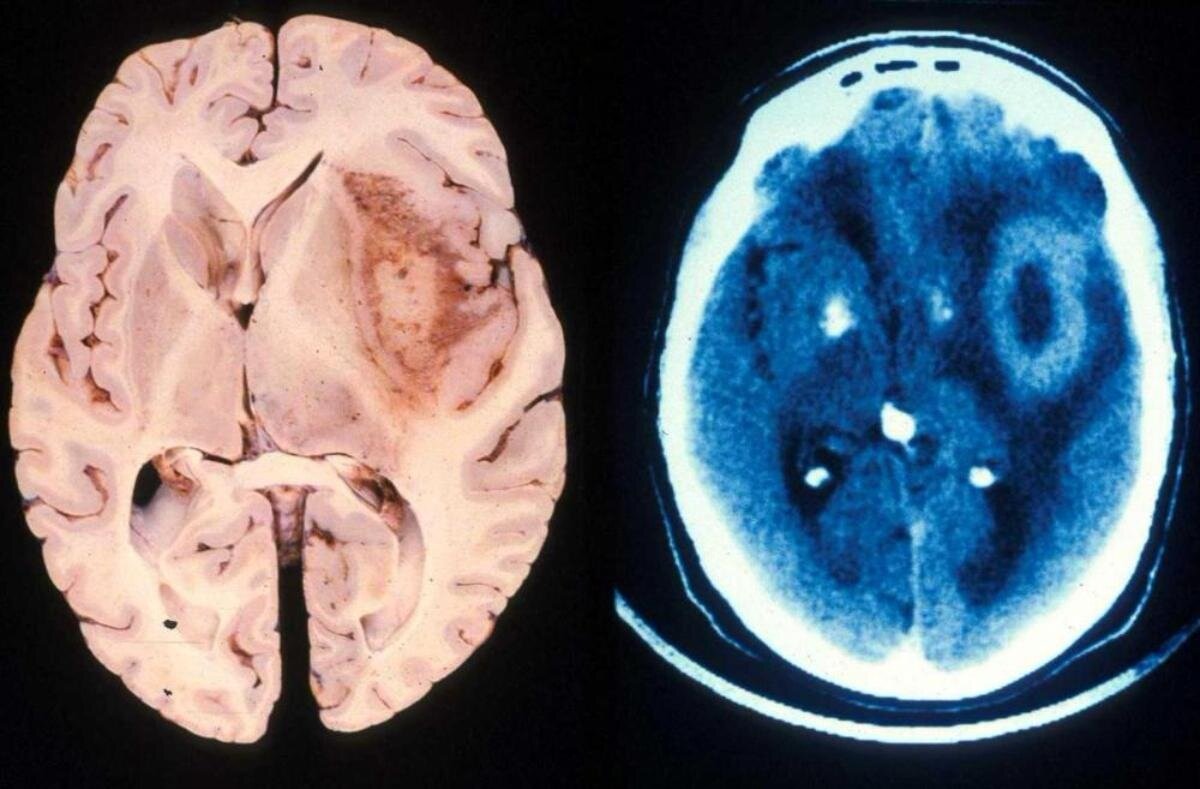

Глиобластома головного мозга считается одним из самых агрессивных видов рака. При этом лечение данного заболевания затрудняется тем, что гемато-энцефалический барьер не дает лекарственному препарату попасть к раковым клеткам, поскольку защищает мозг от токсинов.